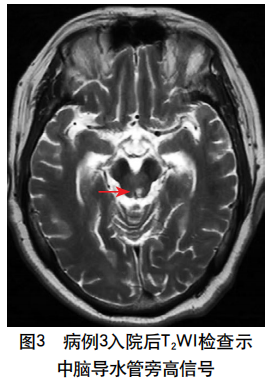

摘要:肥大性下橄榄核变性在临床上较为罕见,其典型临床表现包括腭肌阵挛、共济失调、声音嘶哑和眼部症状,而以四肢阵发性震颤为突出表现的患者则更为罕见,此类患者易被漏诊或误诊。本文报道1例继发于脑干(右侧脑桥和中脑)出血、以四肢阵发性震颤为突出表现的肥大性下橄榄核变性患者,介绍其诊断、治疗及随访情况,并结合相关文献探讨此类患者的临床特点,总结其解剖基础、影像学表现、诊断与治疗要点,以提高临床医师对该病的